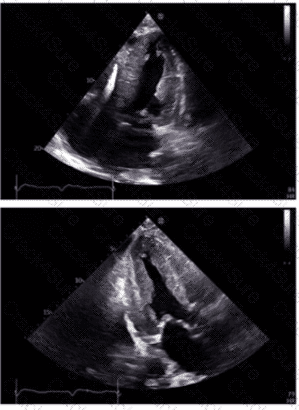

Which is the most likely abnormality represented in these images from a 48-year-old man with shortness of breath?

Which diagnosis is most consistent with the findings in these images?